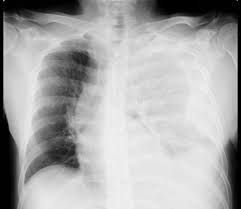

Hemothorax symptoms

Symptoms include: Shortness of breath. Rapid, shallow breathing. Chest pain. Low blood pressure (shock) Pale, cool and clammy skin. Rapid heart rate. Restlessness. Anxiety.